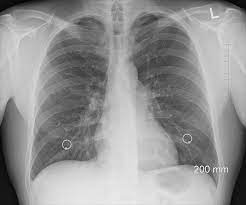

Care guide for lung cancer. Symptoms of lung cancer develop as the condition progresses and there are usually no signs or symptoms in the early stages. The main symptoms of lung cancer include Lung cancer is the deadliest type of cancer, causing more than 150,000 deaths annually in the united states. Cancer cancer is the second most common cause of death cancer has become more common during the 20th century, not because of pollution several human viruses have been shown to cause cancer. See pictures of lung cancer. Lung cancer check up _affect humans and lung cancer is a prominent one. Possible causes, signs and symptoms, standard treatment options and means of care and support. Usually, wheezing occurs when the airways in the lungs become blocked or inflamed. Of course, if you are. You may think it's irrelevant, but chronic shoulder pain can sometimes be the result of a tumor that is pressuring the nerves in the armpit, leading to tingling sensations, aches, and shooting. Learn about lung cancer early warning signs, symptoms and treatments. There are several signs of lung cancer that are relatively common, although they can be subtle and easily attributed to something else.

Symptoms Of Lung Cancer Signs Include Fingering Fr24 News English from dl.img-news.com Lung cancer (cancer of the lung) is common worldwide. A cough that will not go away, and gets worse over time. Treatments are available to decrease signs and symptoms and to help you live longer. Simptom clippings rigler (place of entry of the bronchus). For instance, researchers hoping to reduce the risk of lung cancer in. Chest pain that is not just in one area of your chest. Once lung cancer has spread beyond the lungs, it's generally not curable. Of course, if you are.

The main symptoms of lung cancer include Lung cancer may not cause signs or symptoms in its early stages. See pictures of lung cancer. Anyone can get lung cancer. Usually, wheezing occurs when the airways in the lungs become blocked or inflamed. You may think it's irrelevant, but chronic shoulder pain can sometimes be the result of a tumor that is pressuring the nerves in the armpit, leading to tingling sensations, aches, and shooting. What are the symptoms of lung cancer? If this symptom happens after climbing stairs, bring if the airways become blocked, constricted or inflamed, the human lungs will produce a wheezing or whistling sound when breathing. Lung cancer has almost 20 types and can affect both genders. Lung cancer is the third most common cancer and the main cause. What are lung cancer symptoms and signs? These types of lung cancer grow differently and are treated differently. Of course, if you are.